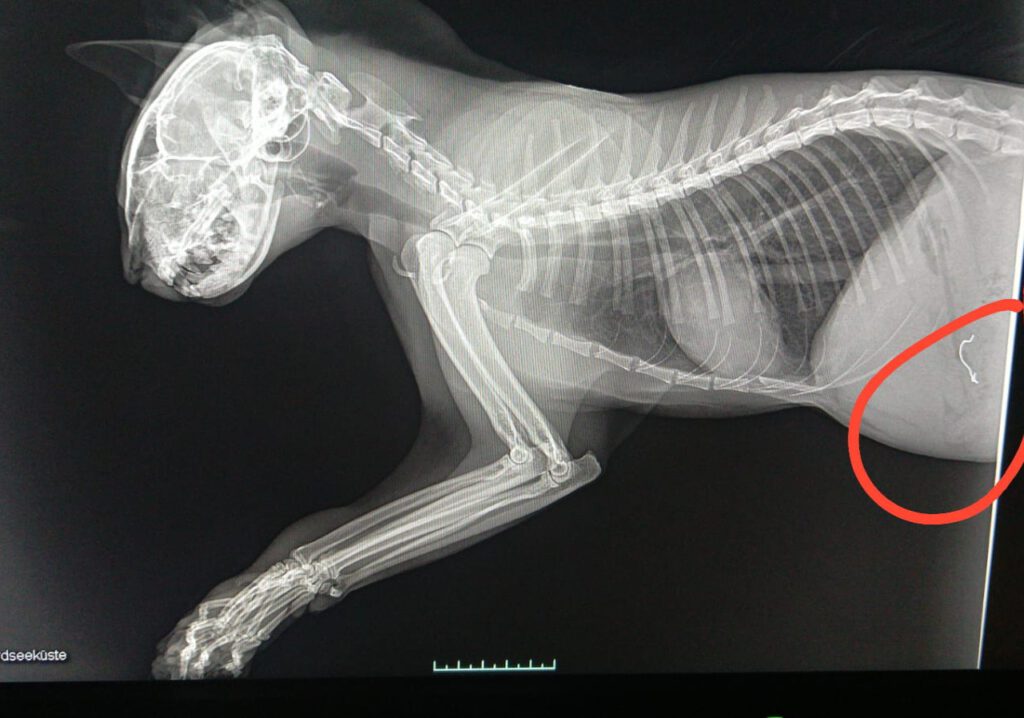

In der anschließenden Behandlung stellte sich heraus, dass die Katze neben erheblichen Verletzungen an der Pfote auch metallische Gegenstände, vermutlich die Befestigung des Köders, in Körper hatte. Die Veröffentlichung der Röntgenbilder wurden vom Tierarzt genehmigt.